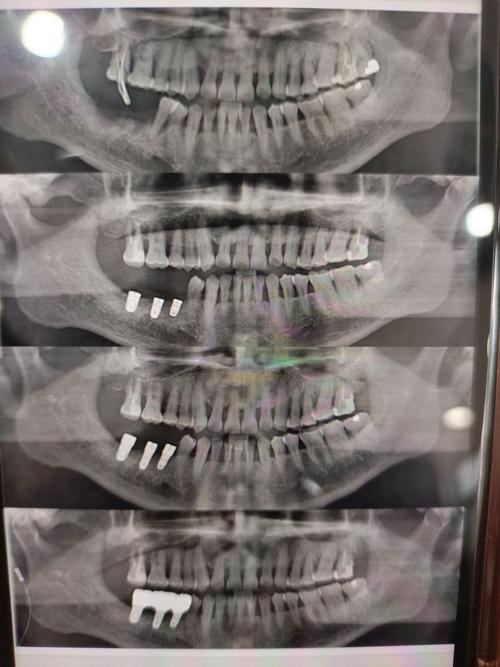

为规避风险,患者需从多维度筛选机构,首先核查资质,确保机构具备口腔种植专科资质,医生持有《医师资格证书》和《医师执业证书》,且种植牙案例不少于500例,其次考察医生背景,优先选择有公立医院工作经历、擅长复杂病例(如骨量不足、全口种植)的医生,可通过面诊时询问其具体案例和手术方案细节判断专业性,设备方面,确认机构是否配备CBCT、种植机、无菌手术室等必备设备,数字化设备(如动态导航系统)是加分项,口碑评价可通过第三方平台(如卫健委官网、大众点评)查看患者真实反馈,重点关注是否有投诉记录及术后效果展示,要求机构提供书面报价单,明确种植体品牌、基台类型、牙冠材质及是否包含术后复查费用,避免隐形消费。